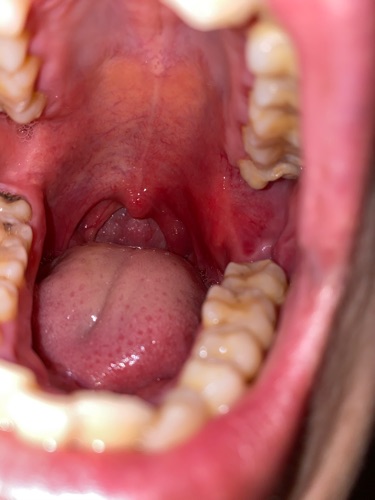

Chào bác sỹ . Tôi mới nhổ răng khôn đk 20 ngày . Bgiờ trong miệng tôi tự nhiên thấy đau . Có hiện tượng sưng đỏ . Mỗi lần nhuốt nước miếng và thức ăn là rất đau . Xin hỏi bác sĩ là tôi bị làm sao ạk ? Và có cách nào để khắc phục không ạk ? Mong bác sĩ rúp đỡ